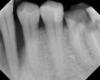

Это нижняя шестёрка, депульпированная приблизительно в 2000 году и залитая резорцином. Видны сломанные инструменты. В прошлом году каналы пытались перепломбировать, но один корень не смогли пройти до конца и перфорировали в бок, часть пломбировочного материала вышла в десну. Но этот зуб абсолютно не беспокоит, не шатается и не гноится. Что с ним посоветуете делать?

Также на снимке виден клык, он тоже гноится и воспаляется периодически.